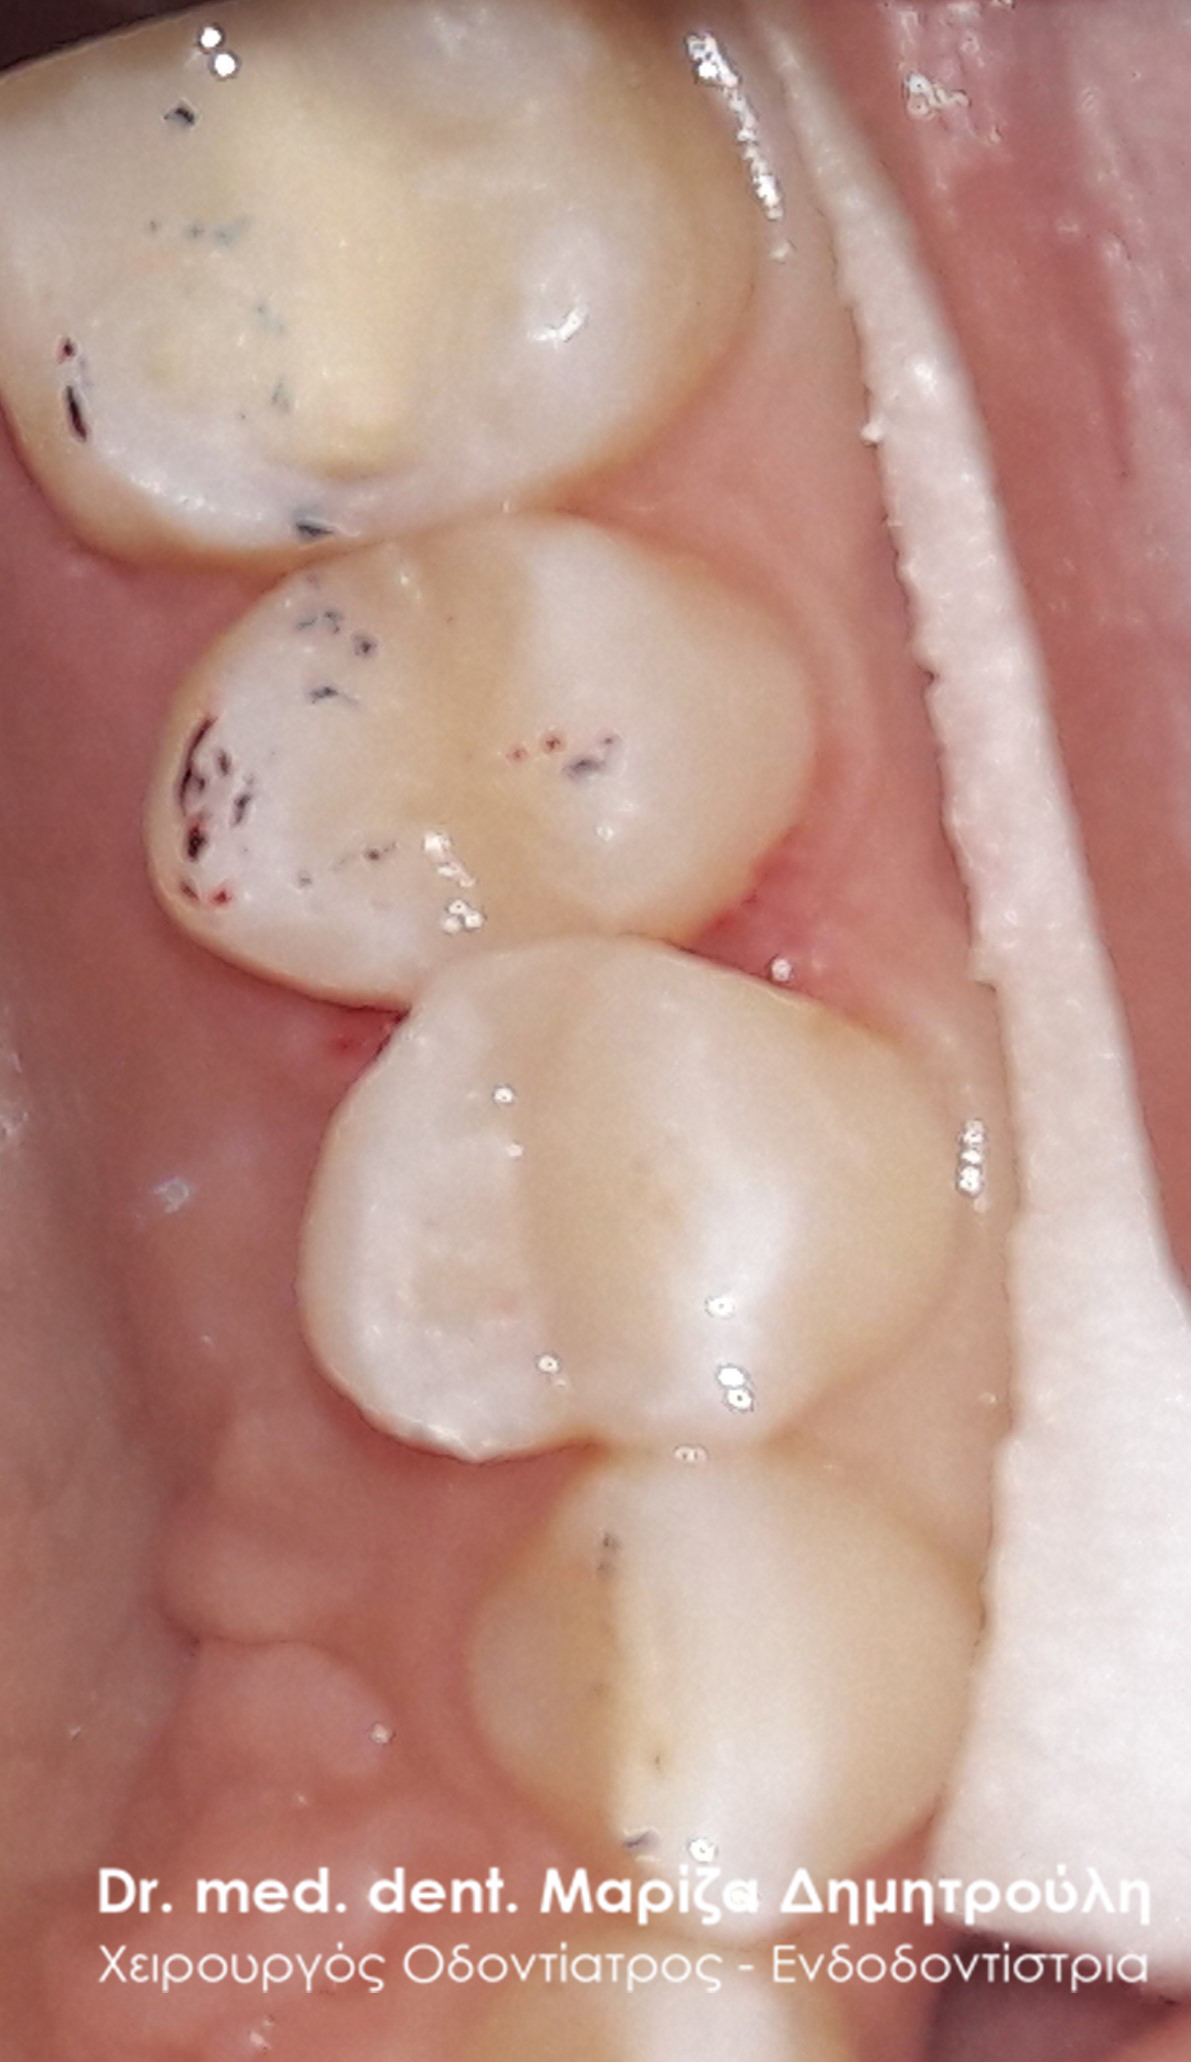

Η ασθενής είχε αντικαταστήσει πριν 2 μήνες 2 σφραγίσματα ( στον 1ο γομφίο και στον 1ο προγόμφιο) στην αριστερή πλευρά της άνω γνάθου. Ανέφερε οτι από τη στιγμή εκείνη υποφέρει από έντονους πόνους. Μετά την κλινική εξέταση διαπιστώθηκε η παρουσία τερηδόνας στο 2ο γομφίο και στο φρονιμίτη. Αποφασίστηκε η αποκατάσταση των τερηδονισμένων δοντιών με λευκά σφραγίσματα σύνθετης ρητίνης. Όσον αφορά τα δόντια με την ευαισθησία πραγματοποιήθηκε αντικατάσταση τους με προσωρινό καταπραυντικό υλικό σφραγίσματος. Σε επόμενο ραντεβού πραγματοποιήθηκε η τελική αποκατάσταση των δοντιών αυτών με λευκά σφραγίσματα ρητίνης.

ΠΡΙΝ

META